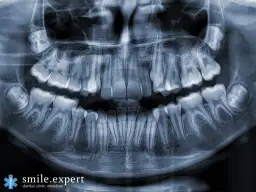

Kwas fosforowy i cytrynowy cisi niszczyciele twojego szkliwa

Wiele popularnych napojów gazowanych, takich jak cola czy lemoniady, zawiera w sobie kwasy głównie kwas fosforowy i cytrynowy. Ich pH jest bardzo niskie, często w zakresie 2,5-3,5, co czyni je niezwykle agresywnymi dla naszych zębów. To właśnie te kwasy, a nie cukier, są głównymi sprawcami demineralizacji, czyli rozpuszczania szkliwa. Proces ten osłabia zęby, czyniąc je bardziej podatnymi na próchnicę. Co więcej, gdy szkliwo ulega erozji, spod niego zaczyna prześwitywać zębina, która ma naturalnie żółtawy odcień, co sprawia, że zęby wydają się ciemniejsze. Osłabione zęby są również bardziej narażone na uszkodzenia mechaniczne.

Erozja zębów: Dlaczego napoje "zero" wcale nie są bezpieczne?

Powszechnym mitem jest przekonanie, że napoje gazowane w wersjach "zero" (bez cukru) są bezpieczniejsze dla zębów. Niestety, to nieprawda. Chociaż nie zawierają cukru, który jest pożywką dla bakterii wywołujących próchnicę, to nadal zawierają te same kwasy, które powodują demineralizację i erozję szkliwa. Niezależnie od obecności cukru, niskie pH tych napojów jest równie szkodliwe dla struktury zęba. Dlatego też, jeśli zależy nam na zdrowiu szkliwa, powinniśmy ograniczyć spożycie wszystkich napojów gazowanych, niezależnie od tego, czy są słodzone cukrem, czy słodzikami.Proste triki, które uratują twoje zęby przed działaniem kwasów